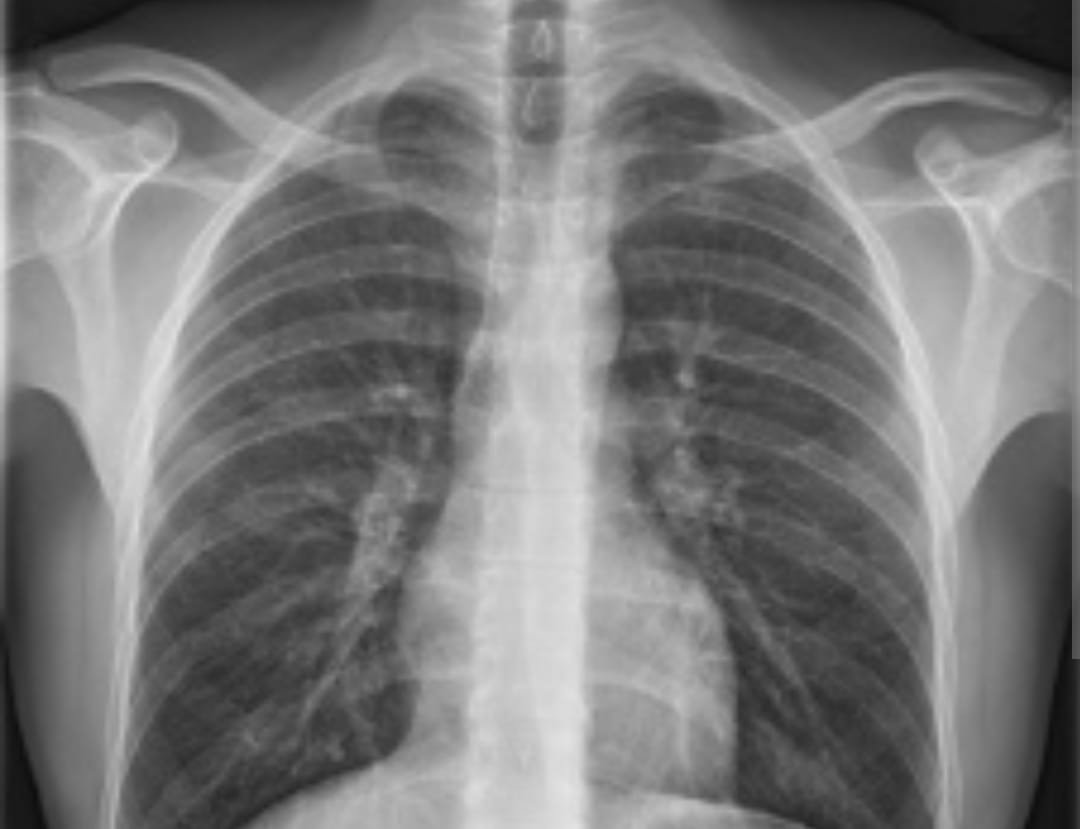

Aprobaron en Argentina un tratamiento innovador contra el cáncer de pulmón

Ahora, Argentina acaba de dar un paso importante en la lucha contra esta patología: la Administración Nacional de Medicamentos, Alimentos y Tecnología (ANMAT) autorizó un tratamiento que combina inmunoterapia con quimioterapia, esta opción terapéutica está destinada a pacientes con cáncer de pulmón de células no pequeñas (CPCNP) que no se encuentren en proceso de metástasis, y se administra antes de realizarse una cirugía.

Esta opción terapéutica (nivolumab) podrá administrarse para personas con cáncer de pulmón de células no pequeñas, que comprende entre el 85 y 90% de los casos de cáncer de pulmón